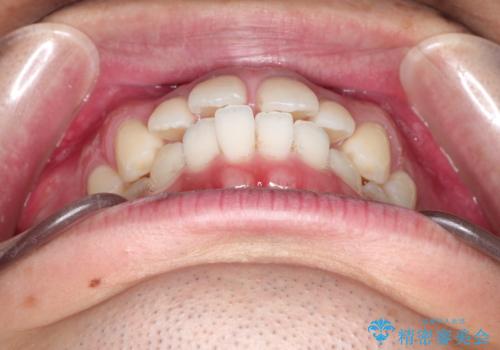

- 上の前歯の隙間と口元を下げたとのことで来院されました。

上顎正中離開と、口唇の突出感がありました。

上下左右の歯を1本ずつ抜歯しして、上顎の前歯を後方に移動させるのと、正中の隙間を閉じる計画としました。

装置はなるべく目立たないものをご希望でしたので、ハーフリンガルを選択されました。

抜歯をせず上顎の正中離開のみの矯正もできましたが、患者様と相談して口元の改善も同時に行うために抜歯矯正の計画としました。